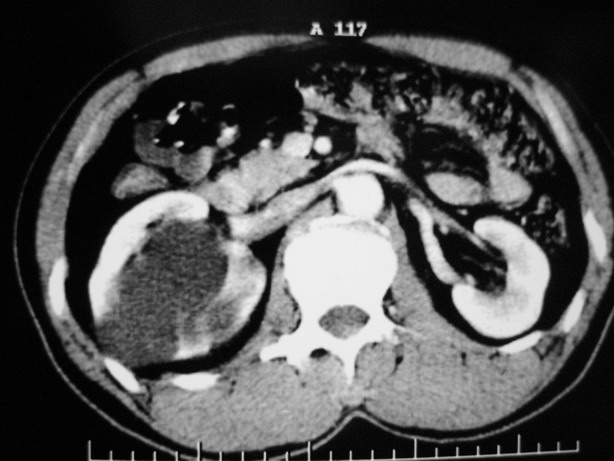

男性,48,体检发现,平时无症状。

增强:

肾盂旁多囊性占位,有实性成分,增强有轻度强化,收集期病变内无造影剂显影。诊断肾盂旁囊肿,有实性成分无法解释,查书后诊断为:多房性囊性肾瘤!!不知大家同意否?????????对本病知道不多,望大家不吝赐教!!

右肾多发囊性低密度影,囊内有增强的隔及实性组织,考虑囊性肾癌。